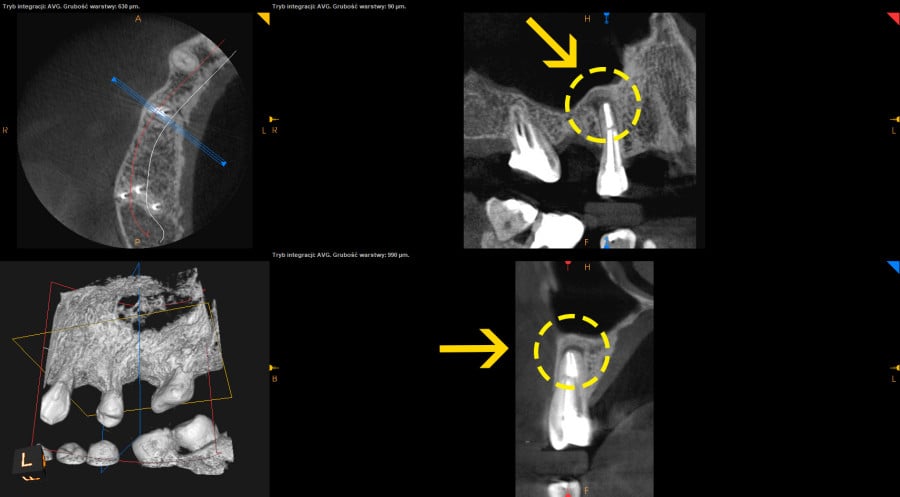

• Po wykonaniu tomografii volumetrycznej zęba 15 stwierdzono rozległą zmianę okołowierzchołkową.

• Przeprowadzono leczenie endodontyczne z użyciem mikroskopu, odbudowę na wkładach z włókna szklanego i zlecono kontrolną tomografię po 6 miesiącach.